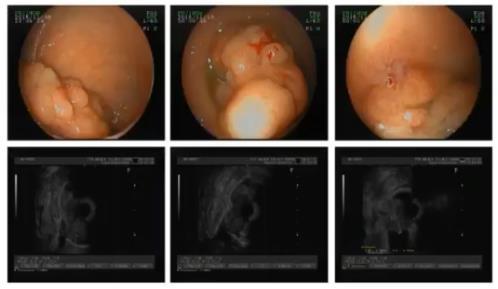

下面,李爱民教授以一个病例为例,分析了超声内镜在术前评估中的应用价值:

53岁男性,主诉为便血3月,于加重11天;肠镜见直肠巨大肿物。